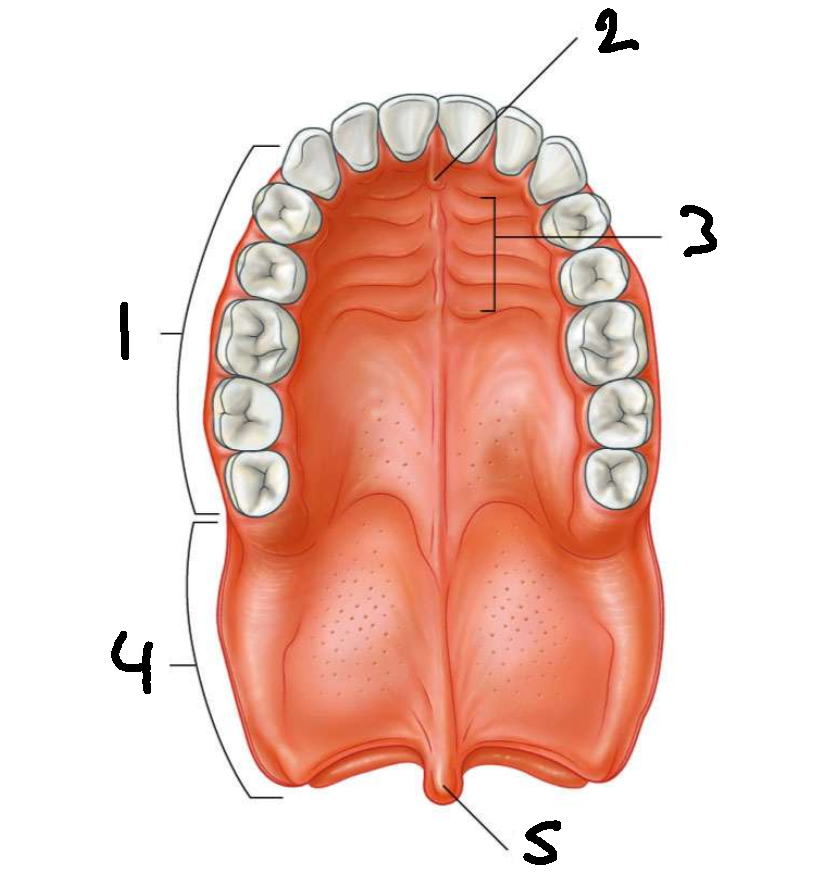

What is 1?

hard palate

What is 2?

incisive papilla

What is 3?

palatine rugae

What is 4?

soft palate

What is 5?

uvula